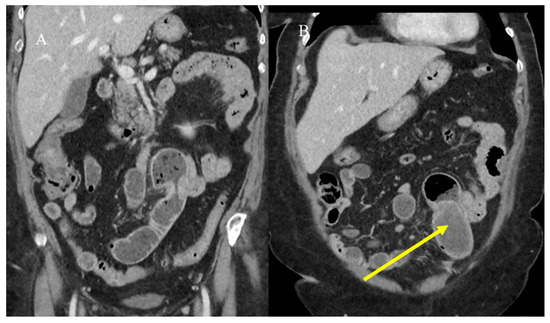

2.3. Small Bowel Tumor Presentation in Emergencies with Intestinal Intussusception